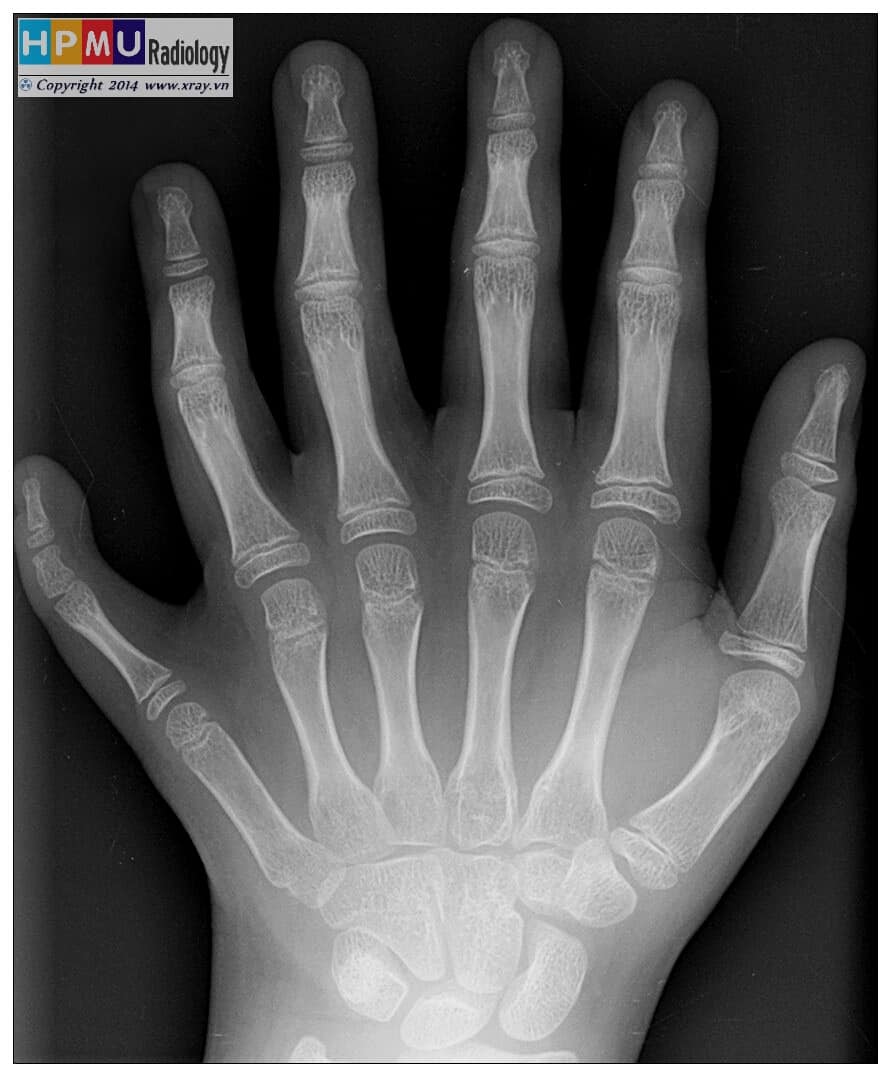

– Loại III: ở trên ngoài, chiếm 75%III. Dị tật chi trên

1. Thiếu xương quay

– Nguyên nhân: mẹ bị chiếu xạ, nhiễm virus, hóa chất.

– Phân loại: đầu dưới xương quay ngắn / xương quay thiểu sản / thiếu 2/3 giữa xương quay hay thiếu toàn bộ xương quay.2. Dính xương cẳng tay

– Kèm mất cơ ngửa dài, cơ sấp tròn, cơ ngửa vuông.

– Phân loại: dính hoàn toàn khớp quay trụ trên / dính một phần cổ xương quay kèm trật chỏm xương quay.3. Dị tật dính ngón

– Hay bị dính nhất là ngón 3-4, ngón 4-5, ngón 2-3 hoặc tính toàn bộ. Người da trắng bị dính nhiều hơn người da đen.4. Dị tật thừa ngón

– Đặc điểm của ngón thừa là thường nhỏ hơn, phát triển cũng kém hơn. Cấu trúc của ngón có thể chỉ là tổ chức có da bao phủ đơn thuần, có hoặc không có móng. Cũng có thể có chứa xương như những ngón bình thường khác.

+ Ngón cái thừa, ngón cái chia đôi: Phân loại Wassel: Loại I: Tách đôi ở xương đốt xa / Loại II: Hai xương đốt xa / Loại III: Tách đôi ở xương đốt gần / Loại IV: Hai xương đốt gần / Loại V: Tách đôi ở xương đốt bàn / Loại VI: Hai xương đốt bàn / Loại VII: Thừa ngón cái 3 đốt

+ Thừa ngón út: hay gặp trẻ da đen, có thể bị cả 2 bàn tay, ngón thừa nằm ở bờ trụ xương bàn tay.5. Dị tật phì đại ngón